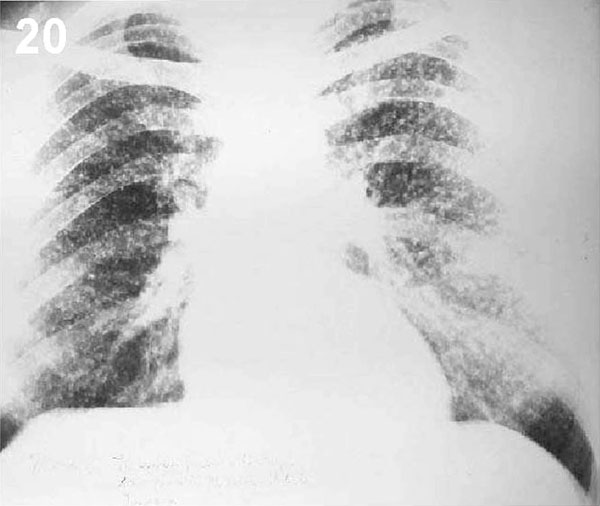

ESQUEMA 20 Comentario placa 20: En esta radiografía, ambos pulmones están sembrados en forma difusa de múltiples nódulos de pequeño tamaño, con elementos reticulares y lineales escasos. Esta imagen micrododular puede ser expresión de granulomas de diversas etiologías (Tbc, silicosis, etc.) o de neoplasias metastásicas. Pase a la placa 21 y ponga especial atención el área marcada con el círculo |